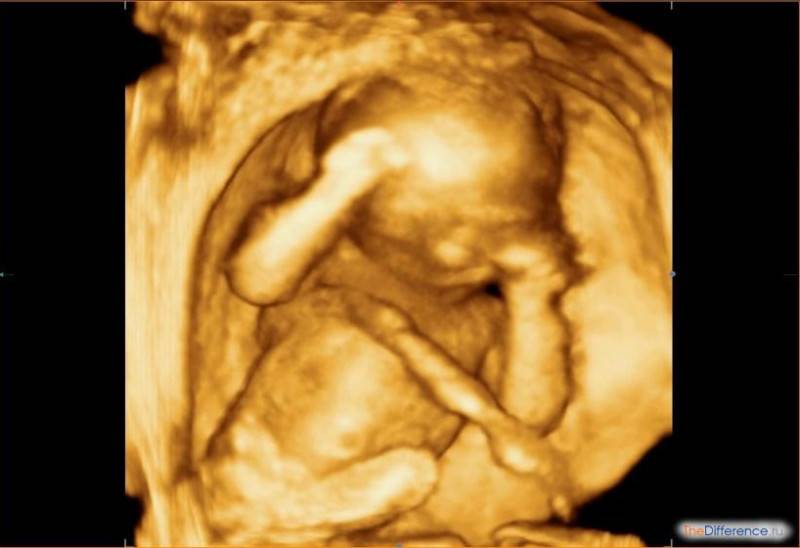

Трехмерное сканирование плода при беременности дает возможность в объемном виде оценить состояние ребенка. Картинка передается на экран аппарата в цветном режиме. Чаще метод используют на втором плановом скрининге, когда четко видны части тела плода.

С помощью 3Д УЗИ делают фотографии и видеозапись движений ребенка в утробе матери. В редких случаях просмотреть малыша не удается из-за того, что он поворачивается спиной. Тогда диагностика проводится через 15–20 минут.

Трехмерное изображение представляется в 3 измерениях — глубине, высоте и ширине. Беременная может увидеть ребенка на экране УЗИ-аппарата в цвете. При этом детально просматривается каждая часть лица и тела, мимика плода.

3D УЗИ. При трехмерном изображении мы получаем объемную и цветную картинку, таким образом можно рассмотреть внешность ребенка во всех подробностях. В отличие от 4D УЗИ, трехмерное изображение статично.